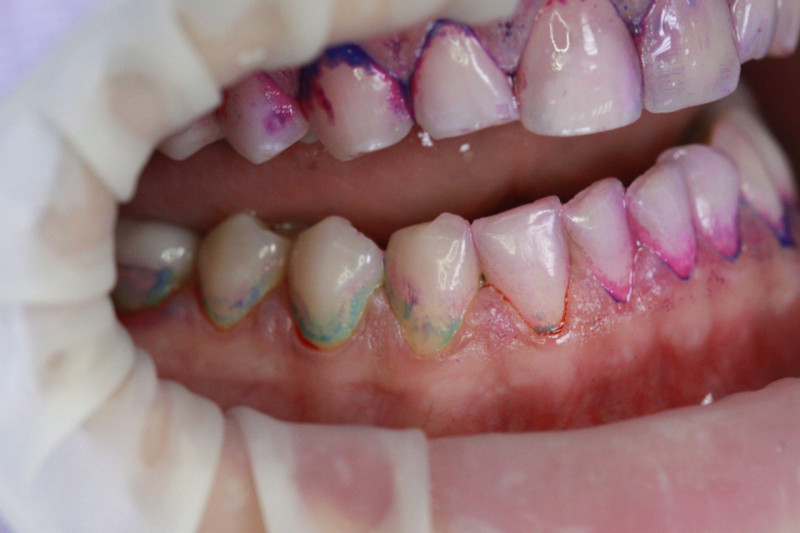

Index Dual работает по принципу селективного окрашивания: свежий налёт (до 24 часов) становится розовым, а зрелый кариесогенный налёт (более 24 часов) — синим.

Высокая контрастность Хорошо видно даже в пришейной зоне

• Чёткая контрастность: Синий цвет настолько интенсивный, что его невозможно спутать с естественной пигментацией или гиперемией дёсен.